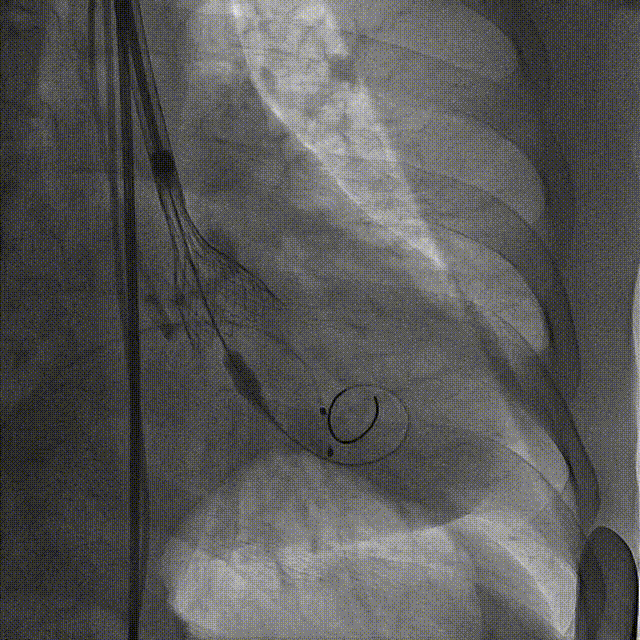

3.TaurusElite AV26号瓣膜定位及释放。瓣膜初始定位0位,开花后120次起搏,释放到工作位后造影显示瓣膜位置较深,形态敞口状,预估释放后存在进一步下滑风险,决定回收调整。

第一次瓣膜初始定位

第一次工作位造影

4.瓣膜第一次释放下滑明显,第二次初始定位瓣上2mm,缓慢释放开花,提拉输送器,快速释放到工作位,造影显示位置良好,少量瓣周漏,决定脱钩

第二次瓣膜初始定位及释放